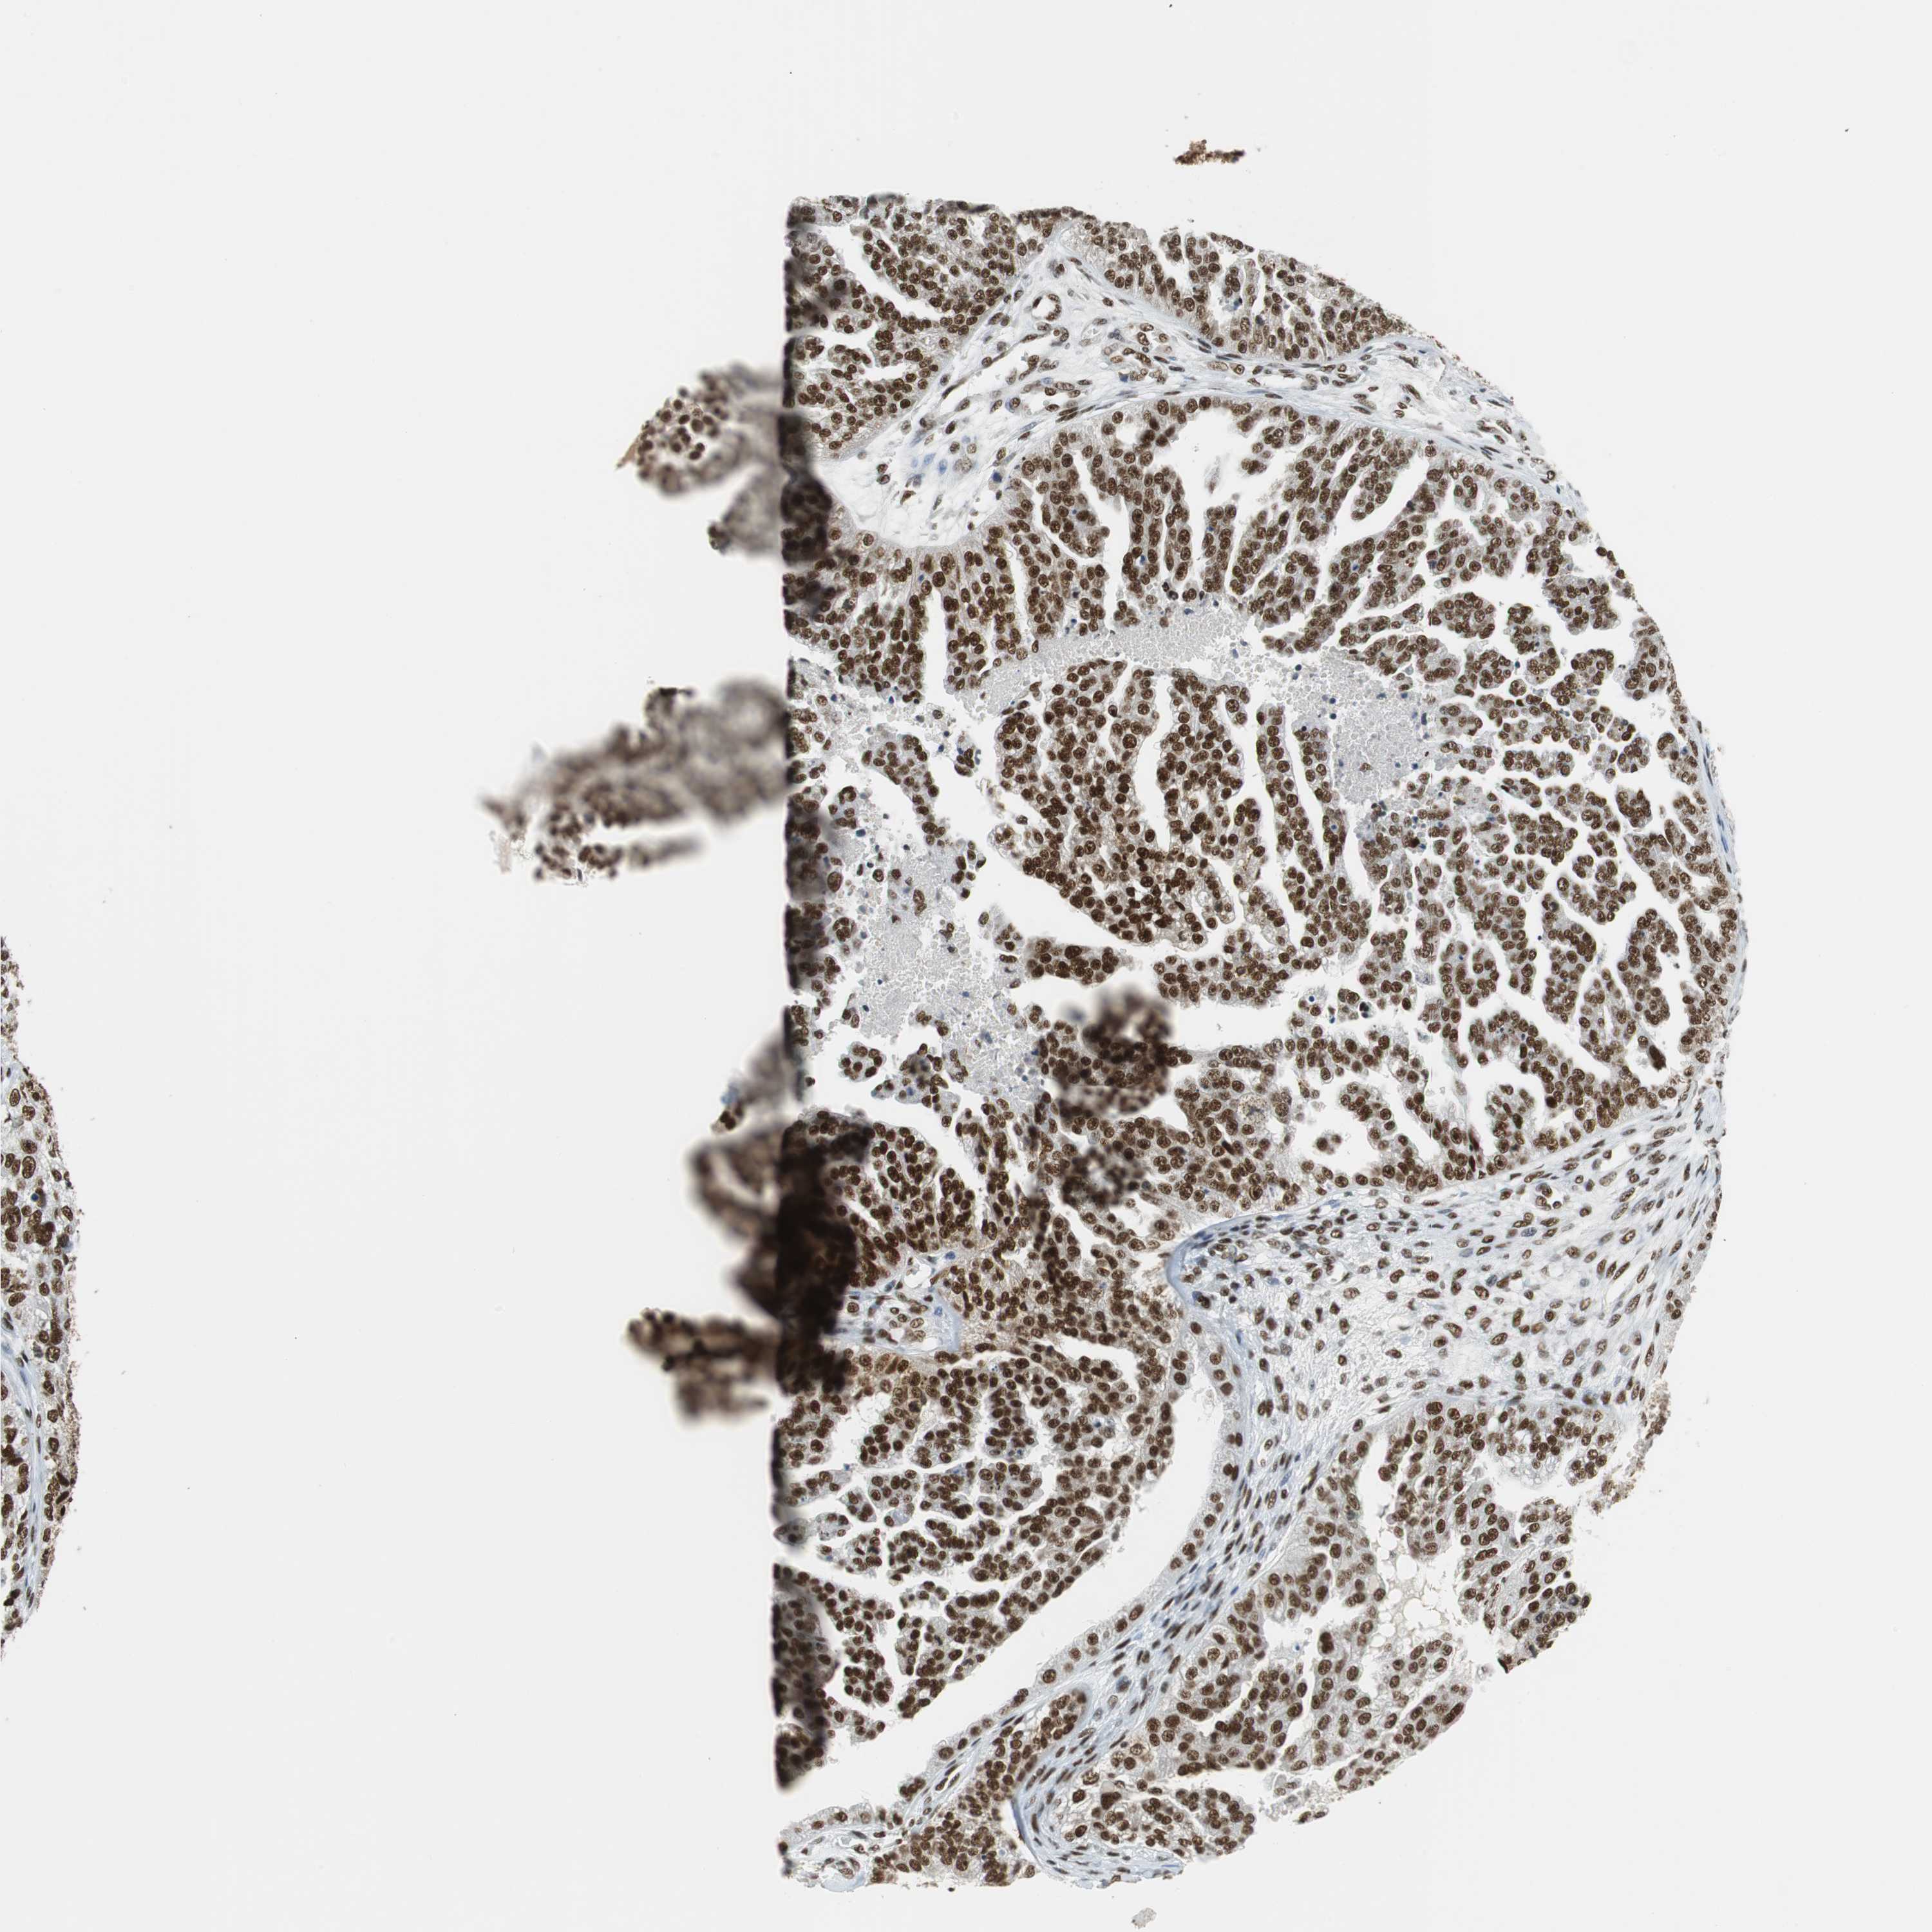

OVARIAN CANCER - Protein expressioni

A mouse-over function shows sample information and annotation data. Click on an image to view it in a full screen mode. Samples can be filtered based on level of antibody staining by selecting one or several of the following categories: high, medium, low and not detected. The assay and annotation is described here.

Note that samples used for immunohistochemistry by the Human Protein Atlas do not correspond to samples in the TCGA dataset.

Antibody stainingi

Antibody staining in the annotated cell types in the current human tissue is reported as not detected, low, medium, or high, based on conventional immunohistochemistry profiling in selected tissues. This score is based on the combination of the staining intensity and fraction of stained cells.

Each image is clickable and will lead to virtual microscopy that enables deeper exploration of all samples and also displays staining intensity scores, fraction scores and subcellular localization as well as patient and tissue information for each sample.

Antibody HPA035174

Cystadenocarcinoma, serous, NOS

Carcinoma, NOS